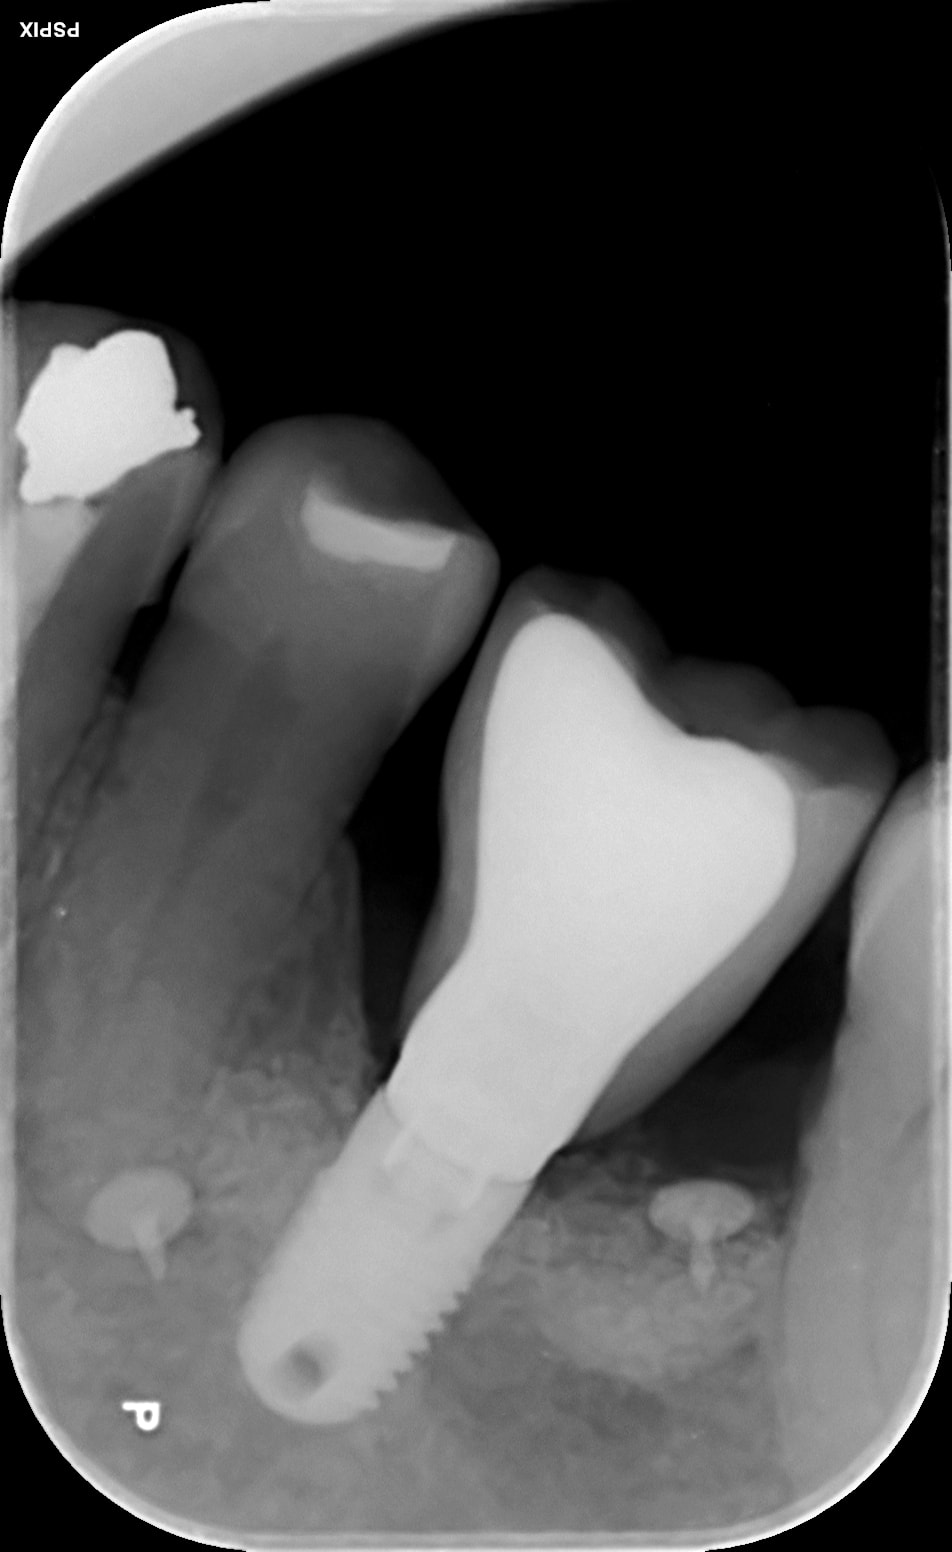

CCM posée il y a 2 ans. Sans problème.

Dévissage il y a quelques jours. Chute. Gingivectomie. Vis de cica.

Je remets aujourd'hui la CCM qui s'adapte impec ( radio ) ; je visse à bloc.

je ne vois qu'une interposition (ou effet retropulsif) de genvice fibreuse. faire une étape avec vis de cicatrisation plus "évasante" , dans ton cas l'image me laisse penser que le col est très enfoui

À la radio, on a l’impression que la vis est en butée.

La gencive fibreuse ne gêne pas , la ccm est à fond ( voir radio )

Pas possible....ton protho t'as fais çà sur une base or....regarde la différence de radio-opacité entre l'implant (titane) la vis (titane là aussi donc même rendu radio) et hex du pilier (plus radio-opaque)

=> c'est pas du titane mais ne base or.....

Avec la radio opacité , en tous cas c'est pas du titane comme dit Pluton, c'est quoi exactement ce pilier "classique" ??